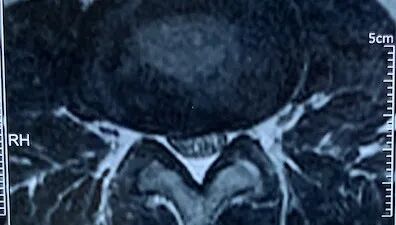

上图中,椎间盘突出仍然存在

然而这个时候,仅仅是临床上患者的症状缓解了。腰椎间盘突出的部位,髓核及纤维环的撕裂修复需要更长的时间。椎间盘突出部位由于解剖结构有所变化,椎间盘的稳定性也受到一定的影响。如果到医院进行磁共振检查,大部分的患者椎间盘突出虽然缩小了一部分,但仍然存在。甚至有很多在日常生活中没有感觉到腰腿疼的人们,如果进行磁共振检查,也会发现有椎间盘突出。